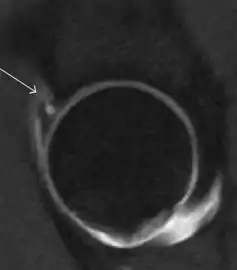

MR arthrography has proven superior in accuracy when compared to native MR imaging. It is considered the best technique to assess the labrum. Knowledge of the normal variable morphology of the labrum helps to differentiate tears from normal variants. A triangular shape is most commonly seen in 66% of asymptomatic volunteers, but round, flattened, and absent labra can also be found in asymptomatic populations. MR arthrography has demonstrated sensitivity over 90% and specificity close to 100% in detecting labral tears. Loose bodies are demonstrated as filling defects surrounded by the hyperintense gadolinium.[1]

Association between labral tears and chondral damage has been demonstrated. This underscores the interaction between cartilage and labrum damage in the progression of osteoarthritis. Chondral damage to the posteroinferior part of the acetabulum as a contrecoup lesion occurs in approximately one-third of pincer cases secondary to persistent abutment on the anterior part of the joint leading to a slight posteroinferior subluxation. This is considered a bad prognosis sign.[1]

MR arthrography can also demonstrate ligamentum teres rupture or capsular laxity, which are debated causes of microinstability of the hip. Elongation of the capsule or injury to the iliofemoral ligament or labrum may be secondary to microtrauma in athletes. MR can demonstrate abnormalities in these cases, such as increased joint volume or a ligamentum teres tear (Figure 9).[1]

Intra-articular osseous causes of pain include several conditions: avascular necrosis (AVN), transient osteoporosis of the hip (TOH), tumors, and stress or insufficiency fractures. All these entities may present with a pattern of bone marrow edema characterized by decreased signal intensity on T1 weighted images and increased signal intensity on fluid sensitive sequences, such as fat saturated T2-weighted or STIR images. When there is no evidence of a focal lesion associated with the edema pattern, TOH is suspected. When a band of low intensity is seen inside the edematous area, the shape and length of this band become important. It is generally convex to the articular surface in the case of subchondral stress or insufficiency fractures, whereas it is concave, circumscribing all of the necrotic segment, in cases of AVN. When doubts do persist, gadolinium-enhanced MRI tends to show that the proximal portion beyond the band is enhanced in fractures but is not in AVN.[1]

MRI has been shown to have 100% sensitivity and specificity in prospective studies of occult hip fractures. These fractures were diagnosed by bone marrow edema and a low signal fracture line, mainly on T1 or T2 weighted images (Figure 10).[1]

Figure 10:

Stress femoral neck fracture in a young athlete barely visible in X-ray film as a sclerotic line (arrow)[1]

In this case, Tc 99 scintigraphy shows a band of uptake[1]

Furthermore, T1 (left) and DP fat saturated (right) weighted MR images showed the fracture line and a pattern of edema.[1]